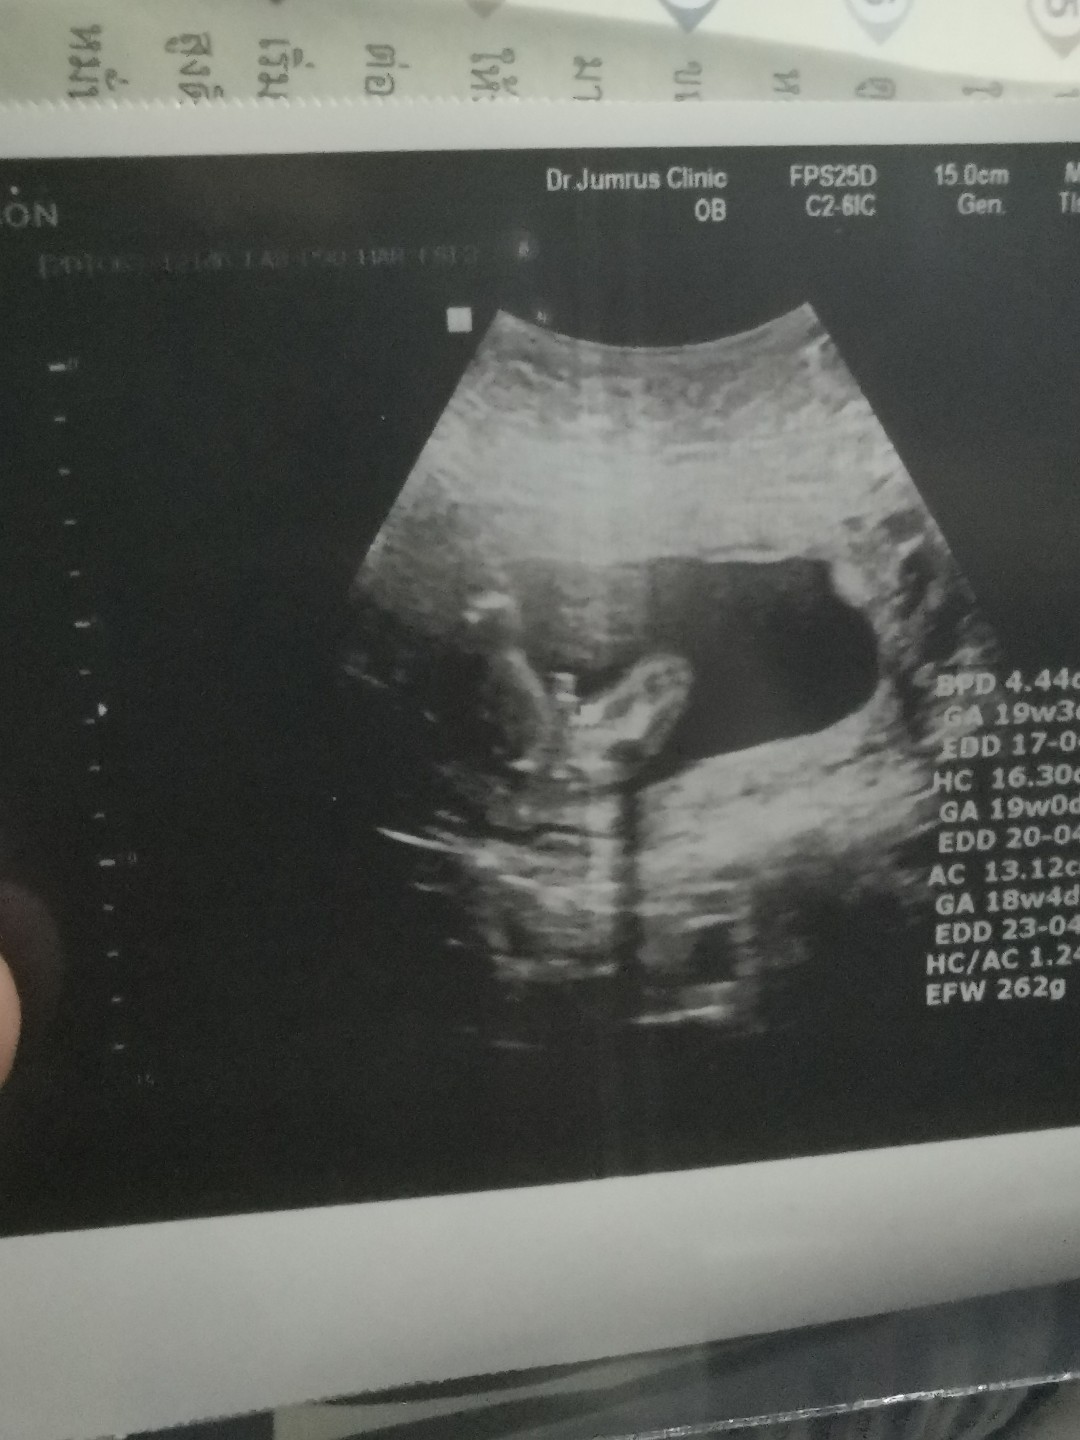

พึ่งซาวด์วันนี้ค่ะ อยากได้ผช. ได้สมใจ ?❤️?